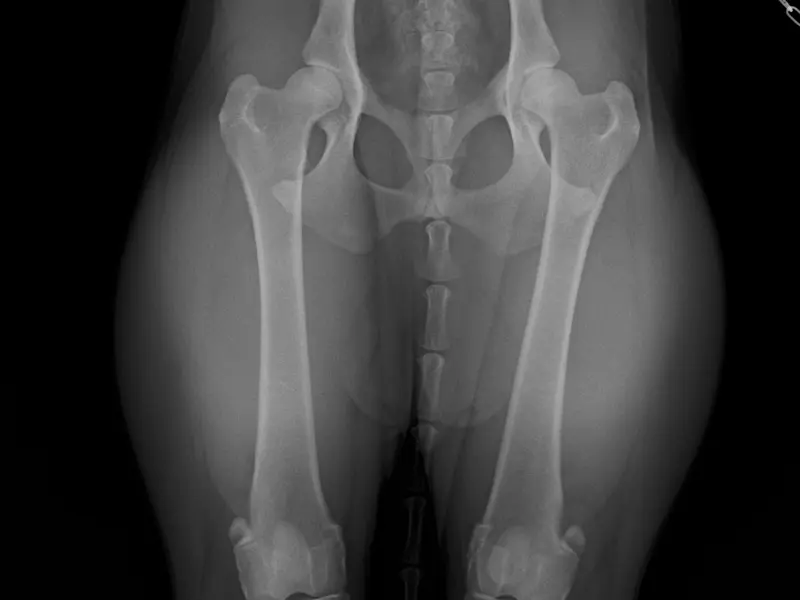

• bei Verschleißerscheinungen oder Fehlbildungen, z. B. HD, ED, Arthrose, Patellaluxation

Gezielte physiotherapeutische Maßnahmen vor und nach einer OP können die Heilungsphase deutlich verkürzen und den Therapieerfolg langfristig sichern. Mögliche Einsatzbereiche sind z.B. Kreuzbandriss, Frakturen, Gelenkersatz, Patellaluxation,